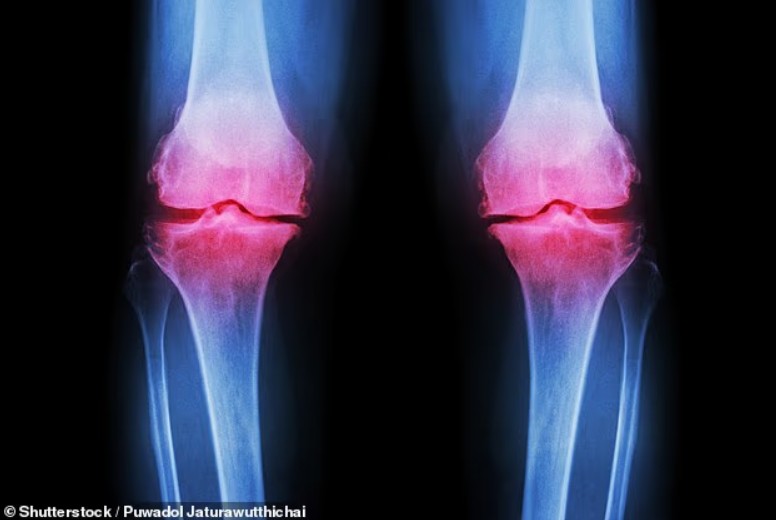

Osteoartriti është një sëmundje që shkakton dhimbje dhe ngurtësi të kyçeve. Rreth gjysma e njerëzve mbi 70 vjeç zhvillojnë një formë artriti, ndërsa në Mbretërinë e Bashkuar osteoartriti prek rreth 10 milionë persona. Tradicionalisht shihej si problem i moshës së mesme e të tretë, por diagnozat tek të rinjtë po shtohen.

Normalisht, kyçet përballen çdo ditë me dëmtime të vogla që organizmi i riparon vetë. Në osteoartrit, kërcet mbrojtëse në skajet e kockave degradohen gradualisht, derisa kyçi nuk arrin më të rigjenerohet.

Osteoartriti zhvillohet gradualisht. Me konsumimin e kërcit, kockat fillojnë të fërkohen me njëra-tjetrën, duke shkaktuar ënjtje, ndjeshmëri dhe dhimbje.